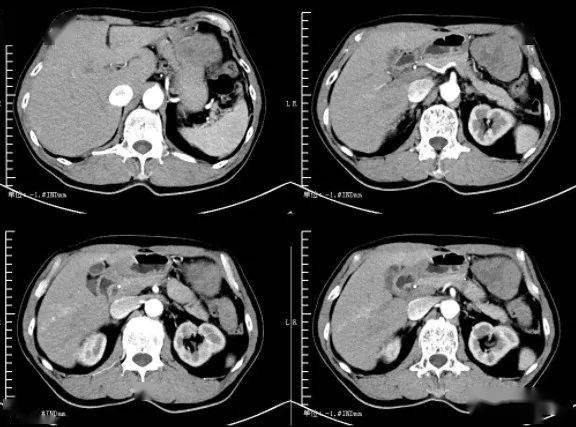

胃平滑肌肉瘤1例ct影像

图片尺寸1022x956